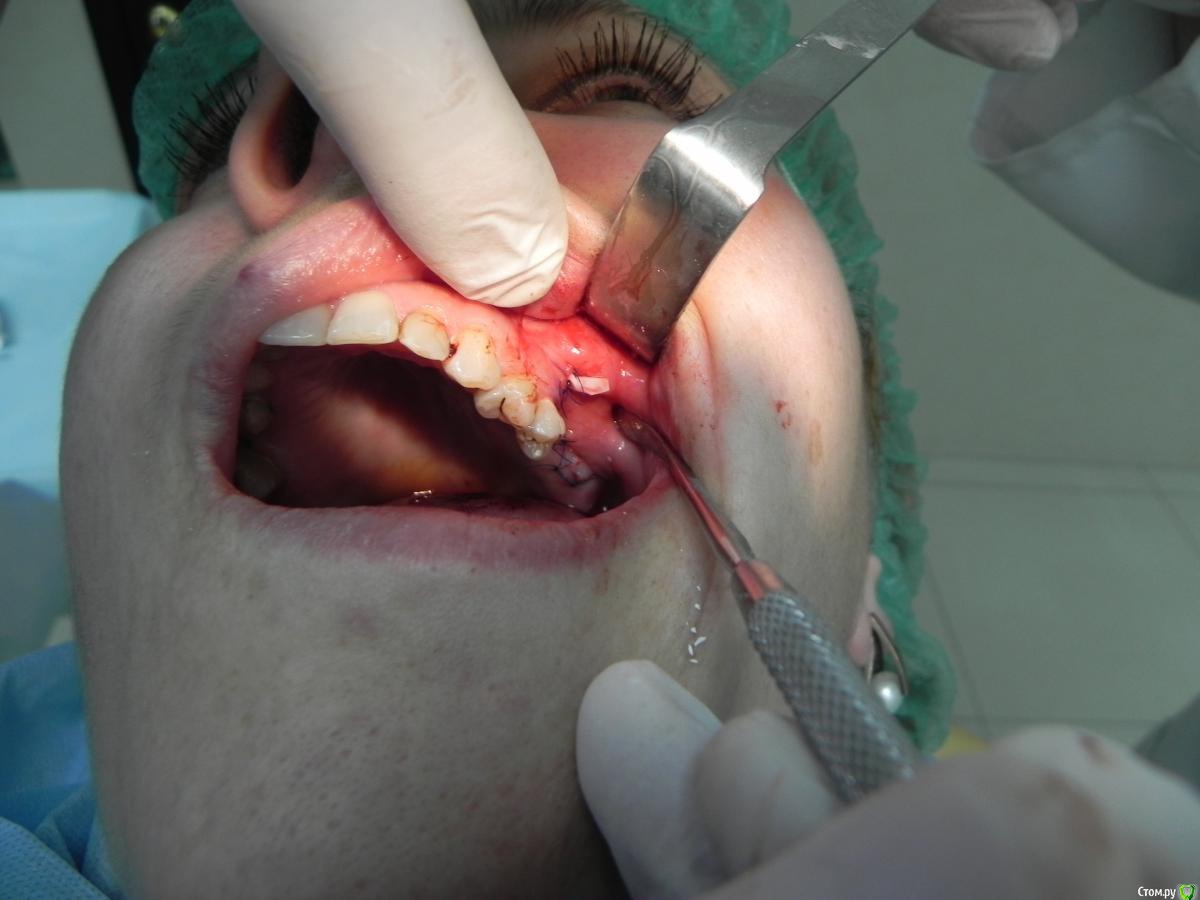

Kostoprav Опубликовано 7 августа, 2015 Поделиться Опубликовано 7 августа, 2015 доступпрепаровка шаровидной костной фрезойпри отслаивании мембраны образовалась маленькая перфа перфорацию" проклеил" коллагеновой мембранойпод мембрану внесен материалмембрана на окноготово может кому из начинающих этот пост полезен будет 1 Ссылка на комментарий

Bier Опубликовано 8 августа, 2015 Поделиться Опубликовано 8 августа, 2015 Коллега, режьте фотки. Кадрируйте т.е есть много очень простых редакторов для этого. А так все прилично, но я бы не стал так близко от костного окна располагать разрезы 3 Ссылка на комментарий

DoctorN Опубликовано 8 августа, 2015 Поделиться Опубликовано 8 августа, 2015 если при синус-лифтинге продлить внутрисосочковый разрез на пару зубов-вертикальный либо совсем не понадобится,либо он будет проходить на удалении от края мембраны. при расхождении швов не так страшно 1 Ссылка на комментарий